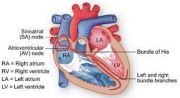

| 2021年7月26日 (一) 20:03 | 心脏起搏传到系统.jpg (文件) |  |

30 KB | Uploaded with SimpleBatchUpload | 3 |

| 2021年7月26日 (一) 20:03 | 心脏电传导系统.jpg (文件) |  |

38 KB | Uploaded with SimpleBatchUpload | 3 |